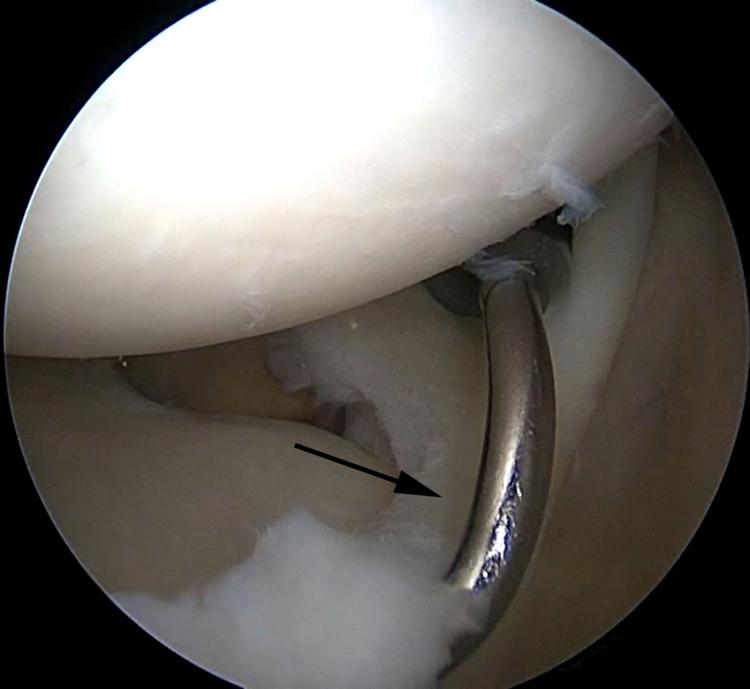

SLAP tears have been a controversial topic in shoulder surgery for decades. The indications for repair of SLAP tears, as well as the methods of repair, have undergone a recent evolution. The use of intra-articular knots for SLAP repair has fallen out of favor because of potential abrasive damage to the rotator cuff and glenohumeral articular cartilage due to knot migration and prominence. In response to this potential iatrogenic injury, arthroscopic techniques have undergone an evolution using advanced techniques with low-profile knotless repairs. We describe our preferred low-profile knotless technique for SLAP repair using LabralTape (Arthrex) in a horizontal mattress configuration.

几十年来,肩袖上盂唇(SLAP)损伤一直是肩部手术中颇具争议的话题。SLAP损伤的修复指征以及修复方法最近都有所发展。由于结的迁移和突出可能对肩袖和肱盂关节软骨造成潜在的磨损损伤,关节内打结用于SLAP修复已不再受青睐。针对这种潜在的医源性损伤,关节镜技术已发展为采用先进技术进行低轮廓无结修复。我们描述了一种使用LabralTape(Arthrex)以水平褥式缝合方式进行SLAP修复的首选低轮廓无结技术。